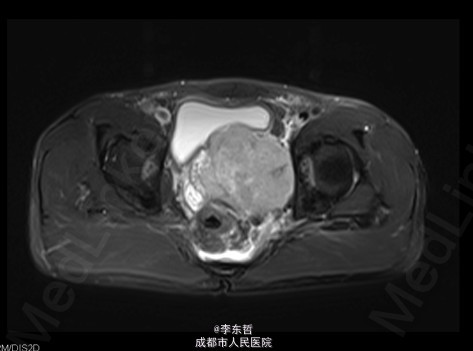

查体:臀部、会阴部、下腹部未触及包块,左下肢前内侧皮肤感觉较对侧减弱,双侧膝反射、跟腱反射正常引出,肛周皮肤感觉减退,直肠指检可触及质韧包块,活动度较差。双下肢肌力5级,双下肢各关节活动度可。 辅查:外院增强CT示:盆腔左侧壁见团块状软组织密度影,密度不均,其内见多发斑块高密度影,病灶大小约9.4*7.6cm,增强后强化不明确。我院X片示:左侧闭孔及耻骨区见不均匀高密度影,大小约6.2*6.7cm。我院MRI示:盆腔左份见长T1长T2肿块影,大小约10.3*7.7*10.5cm,向前推挤膀胱,向右推挤前列腺。我院骨扫描显示:耻骨联合及左侧耻骨支核素浓集。